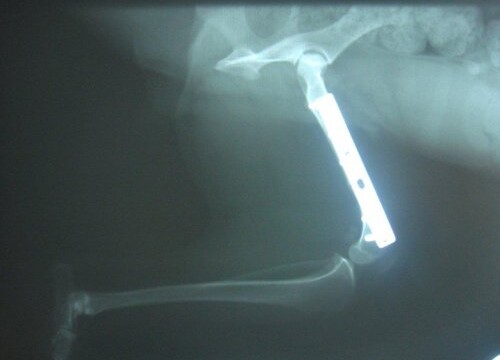

Alle Welpen wurden vermittelt und Tilly wurde am 21.12.2012 bei Dr. Rumpf operiert. Sie hatte einen alten Oberschenkelbruch im linken Hinterbein.

Die OP ist gut verlaufen, Tilly hat eine Platte bekommen und muss im September 2013 nochmals operiert werden. Dabei wird die Platte dann wieder entfernt.

Da der Bruch vermutlich schon mind. ein halbes Jahr alt war, musste bei der OP bei beiden Knochenenden 1,5 cm abgeschnitten werden. Dadurch ist ihr linkes Hinterbein nun verkürzt und Tilly wird immer humpeln. Aber mittlerweile verwendet sie ihr Bein schon wieder mehr.

Ein Kontrollröngten im Jänner 2013 zeigte, das alles in Ordnung ist.

Tilly wurde am 19.2.2013 kastriert und da haben wir nochmal ein Kontrollröntgen machen lassen. Auf diesem Foto kann man sehr gut erkennen, dass der Knochen kürzer ist.